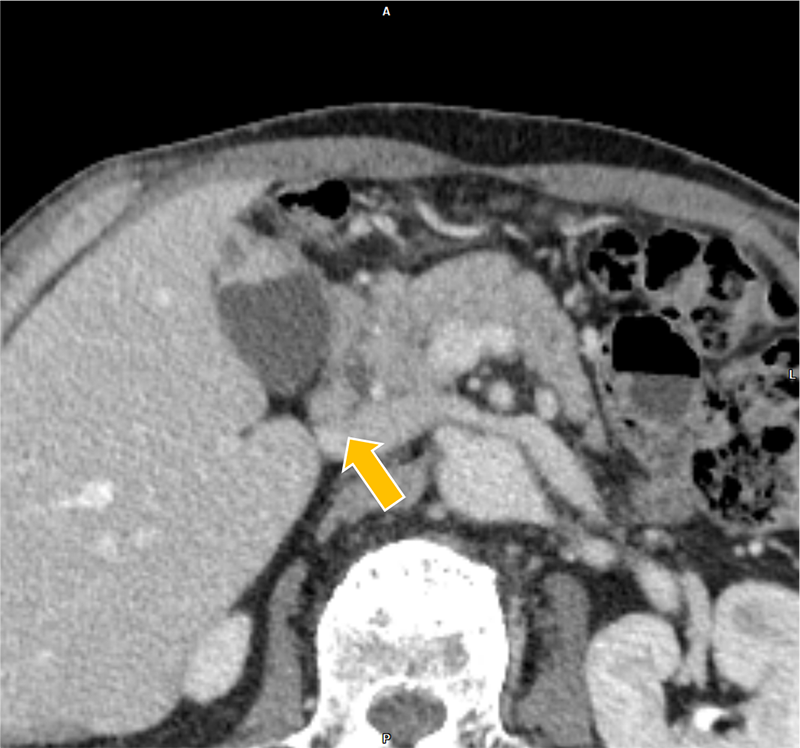

膀胱癌の治療経過観察中、胆嚢癌が疑われ、術前精査目的に肝ダイナミックCTが施行された。胆嚢底部に長径30mm程の腫瘤を認めた。また、胆嚢左側や背側にリンパ節転移を疑う造影結節を認めた。さらに、同CTで前立腺左葉から直腸左側にかけての膿瘍形成が指摘され、後の精査でBCG注入療法に伴う骨盤内BCG感染症が明らかとなった。膿瘍の治療過程で腹膜播種が出現、胆嚢癌は化学療法の方針となった。